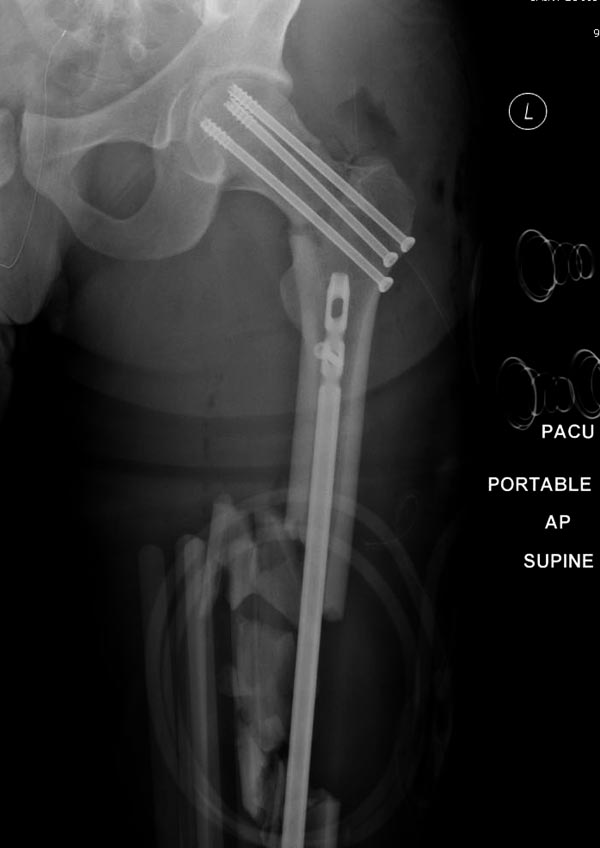

Здесь выставлен ренгенограммы больного, ему 21, травму получил в результате высокоскоростной погони на украденной машине, которая закончилась смертью трех остальных “боевых комрадов”. Начатую коллегой открытую операцию на шейке пришлось закончить мне, установкой винтов и ретроградной фиксацией бедра. Выписка в обычное сроки и наблюдался амбулаторно. Каждый раз напоминали о возможности осложнений ввиде несращения! По истечению 4 месяцев появились признаки варусной деформации. На СТ срезах несращение шейки и бедра. Риминг, замена на более толстый гвоздь и вальгусная остеотомия.

Сразу скажу, что пациент вчера (8.04) прооперирован - артротомия, остеосинтез мыщелков большеберцовой кости канюлированными винтами, открытая репозиция отломков бедренной кости, ретроградный БИОС, остеосинтез надколенника (центральных его отломков) спицами с проволочной петлей. Двухкратная попытка закрытой репозиции шейки на операционном столе после синтеза бедра - абсолютно неэффективна. Учитывая продолжительность и травматичность операции, шейка отложена на 2-й этап. Плечо наверное на 3-й (если вообще делать). Снимки постараюсь предоставить, но чуть позже.